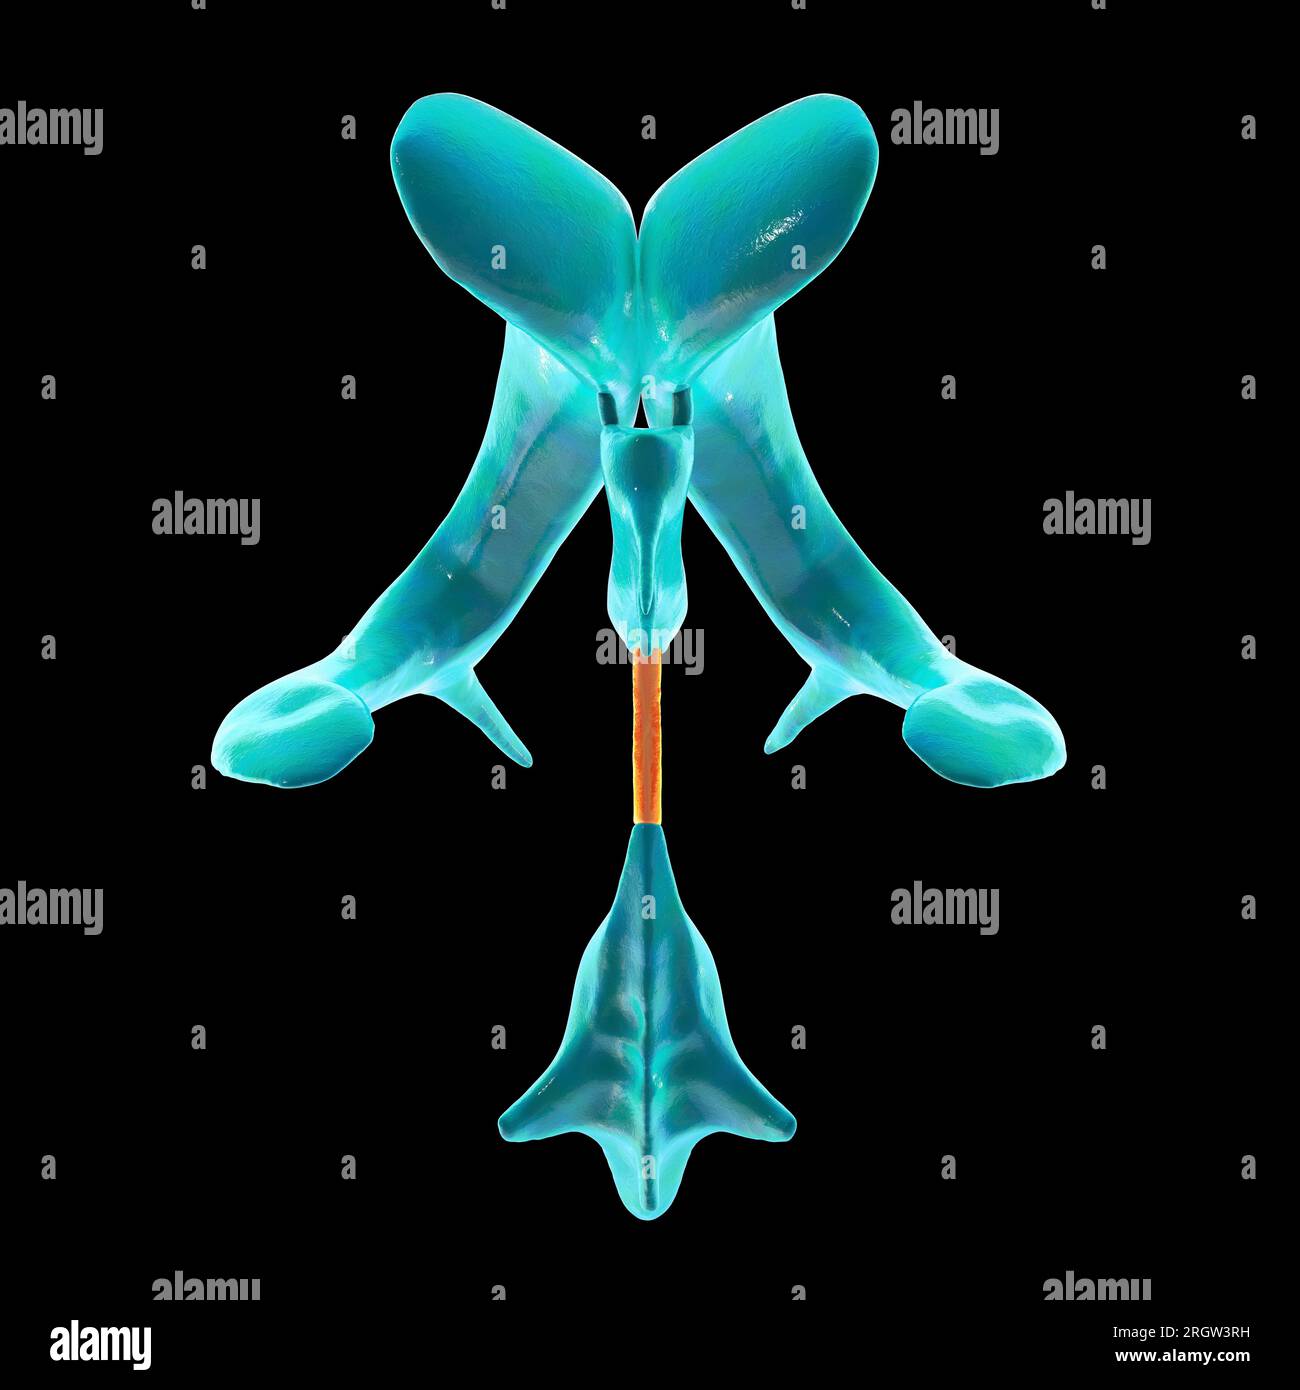

RF2YYB73Y–Computerdarstellung des menschlichen Gehirns mit orangefarbenem Aquädukt und grünem Ventrikelsystem, Darstellung des Liquorflusses (CSF), Draufsicht.

RF2YYB751–Computerdarstellung des cerebralen Aquädukts (orange), eines schmalen Kanals im Mittelhirn, der den dritten und vierten Ventrikel verbindet und den Liquorfluss erleichtert.

RF2YYB74X–Computerdarstellung des cerebralen Aquädukts (orange), eines schmalen Kanals im Mittelhirn, der den dritten und vierten Ventrikel verbindet und den Liquorfluss erleichtert.

RF2YYB75A–Computerdarstellung des cerebralen Aquädukts (orange), eines schmalen Kanals im Mittelhirn, der den dritten und vierten Ventrikel verbindet und den Liquorfluss erleichtert.

RF2YYB754–Computerdarstellung des cerebralen Aquädukts (orange), eines schmalen Kanals im Mittelhirn, der den dritten und vierten Ventrikel verbindet und den Liquorfluss erleichtert.

RF2YYB75B–Computerdarstellung des cerebralen Aquädukts (orange), eines schmalen Kanals im Mittelhirn, der den dritten und vierten Ventrikel verbindet und den Liquorfluss erleichtert.

RF2YYB759–Computerdarstellung des cerebralen Aquädukts (orange), eines schmalen Kanals im Mittelhirn, der den dritten und vierten Ventrikel verbindet und den Liquorfluss erleichtert.

RF2YYB755–Computerdarstellung des cerebralen Aquädukts (orange), eines schmalen Kanals im Mittelhirn, der den dritten und vierten Ventrikel verbindet und den Liquorfluss erleichtert. Rückansicht.

RF2YYB752–Computerdarstellung des cerebralen Aquädukts (orange), eines schmalen Kanals im Mittelhirn, der den dritten und vierten Ventrikel verbindet und den Liquorfluss erleichtert. Rückansicht.

RF2YYB75E–Computerdarstellung des cerebralen Aquädukts (orange), eines schmalen Kanals im Mittelhirn, der den dritten und vierten Ventrikel verbindet und den Liquorfluss erleichtert. Ansicht von unten.